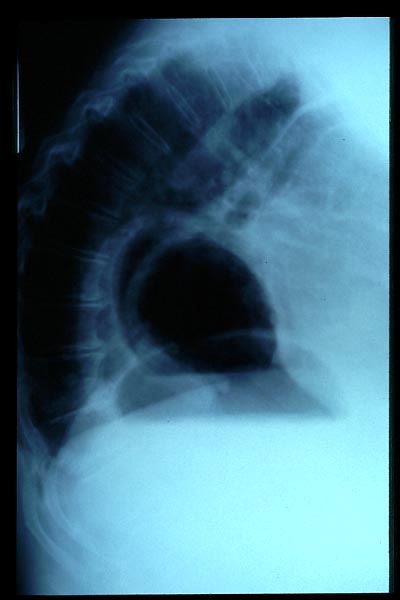

Osteoporosis. Cifosis.